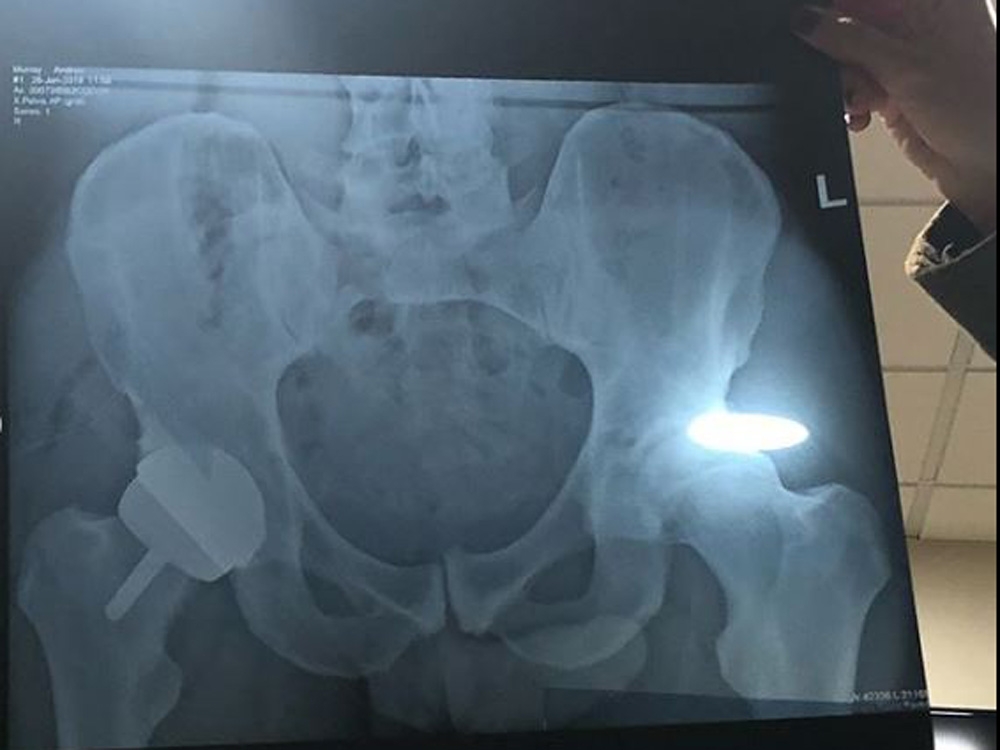

Alongside the post, Murray shared two pictures: one of himself lying in a hospital bed, and the other an X-ray.

“I now have a metal hip as you can see,” Murray continued, “and I look like I’ve got a bit of a gut.”

However, it doesn’t seem like his fans were concerned about Murray’s gut at all. Rather, they spotted what looks like the shadow of his penis at the bottom of his X-ray.

While people poked fun at the sight of the X-ray, it’s actually a thing in the field of radiology known as the Throckmorton sign.

– also known as John Thomas sign – is a term used by radiologists to refer to the direction of where the penis points in relation to unilateral disease.

The common belief is that the penis points to the direction of the medical condition – in Murray’s case, his hip.